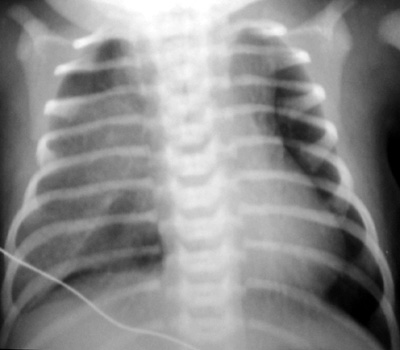

4. What is the most likely diagnosis? | |